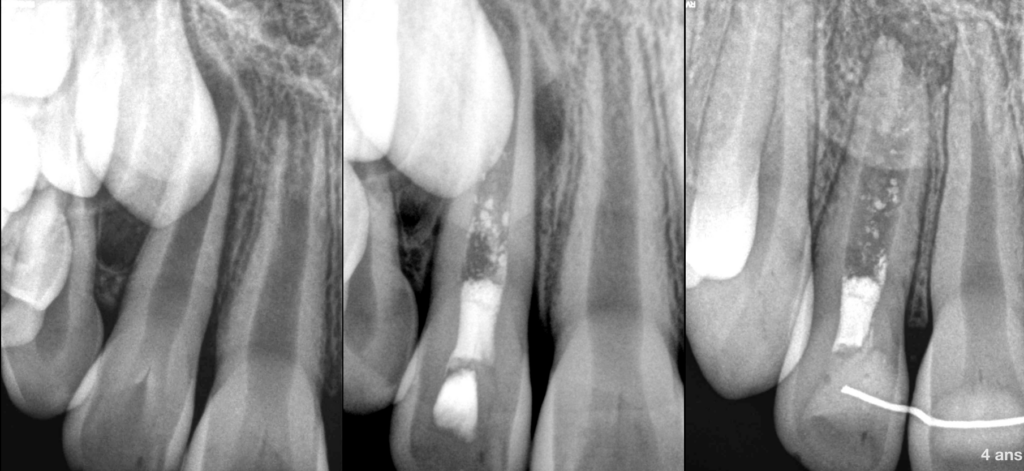

๐ ๐๐ฎ๐ฅ๐ฉ๐ ๐ง๐ฬ๐๐ซ๐จ๐ฌ๐ฬ๐, ๐ฉ๐๐ซ๐จ๐๐จ๐ง๐ญ๐ข๐ญ๐ ๐๐ฉ๐ข๐๐๐ฅ๐ ๐๐ฌ๐ฒ๐ฆ๐ฉ๐ญ๐จ๐ฆ๐๐ญ๐ข๐ช๐ฎ๐

๐ฆท ๐๐๐ง๐ญ ๐ฉ๐๐ซ๐ฆ๐๐ง๐๐ง๐ญ๐ ๐ข๐ฆ๐ฆ๐๐ญ๐ฎ๐ซ๐

๐ ๐๐๐๐ ๐๐ ๐ญ๐ซ๐๐ฎ๐ฆ๐๐ญ๐ข๐ฌ๐ฆ๐ ๐๐๐ง๐ญ๐๐ข๐ซ๐

โ ๐๐๐ฏ๐ข๐ญ๐๐ฅ๐ข๐ฌ๐๐ญ๐ข๐จ๐ง ๐ฬ ๐ ๐๐ง๐ฌ.

๐ Les observations ร 4 ans :

๐น ๐๐๐ฌ๐ญ ๐๐ ๐ฌ๐๐ง๐ฌ๐ข๐๐ข๐ฅ๐ข๐ญ๐ฬ ๐ฉ๐ฎ๐ฅ๐ฉ๐๐ข๐ซ๐ ๐ฉ๐จ๐ฌ๐ข๐ญ๐ข๐

๐น Pas dโaugmentation de ๐ฅโ๐ฬ๐ฉ๐๐ข๐ฌ๐ฌ๐๐ฎ๐ซ ๐๐ ๐๐๐ง๐ญ๐ข๐ง๐ ๐ซ๐๐๐ข๐๐ฎ๐ฅ๐๐ข๐ซ๐

๐น ๐๐ฉ๐๐ฑ๐จ๐ ๐ฬ๐ง๐ฬ๐ฌ๐ ๐๐๐๐๐๐ญ๐ฎ๐ฬ๐

๐น ๐โ๐จ๐ฌ ๐ฉ๐ฬ๐ซ๐ข–๐๐ฉ๐ข๐๐๐ฅ ๐๐ฌ๐ญ ๐ง๐จ๐ซ๐ฆ๐๐ฅ

โ ๐๐จ๐ฎ๐ฏ๐จ๐ง๐ฌ–๐ง๐จ๐ฎ๐ฌ ๐๐จ๐ง๐๐ฅ๐ฎ๐ซ๐ ๐ช๐ฎ๐ ๐ง๐จ๐ญ๐ซ๐ ๐ข๐ง๐ญ๐๐ซ๐ฏ๐๐ง๐ญ๐ข๐จ๐ง ๐๐ฌ๐ญ ๐๐๐๐ข๐๐๐๐ ?

โ๏ธ ๐๐ฎ๐ข !

๐ฏ ๐โ๐จ๐๐ฃ๐๐๐ญ๐ข๐ รฉtait de prolonger la durรฉe de vie de cette dent sur lโarcade en corrigeant un ๐ฉ๐ซ๐จ๐๐ฅ๐ฬ๐ฆ๐ ๐ข๐ง๐๐๐๐ญ๐ข๐๐ฎ๐ฑ/๐ข๐ง๐๐ฅ๐๐ฆ๐ฆ๐๐ญ๐จ๐ข๐ซ๐.

โจ ๐๐ ๐๐จ๐ง๐ฎ๐ฌ aurait รฉtรฉ dโobtenir ๐ฅโ๐ฬ๐๐ข๐๐ข๐๐๐ญ๐ข๐จ๐ง ๐ซ๐๐๐ข๐๐ฎ๐ฅ๐๐ข๐ซ๐ ๐๐จ๐ฆ๐ฉ๐ฅ๐ฬ๐ญ๐.